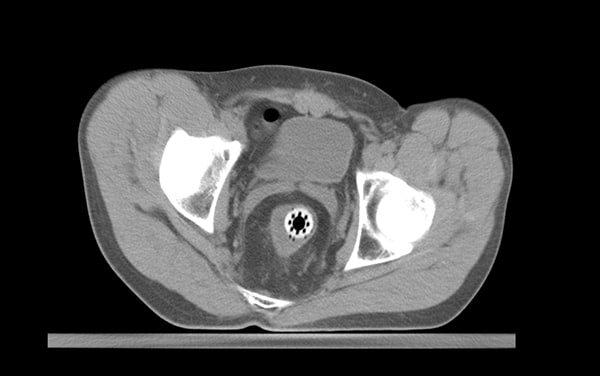

CT